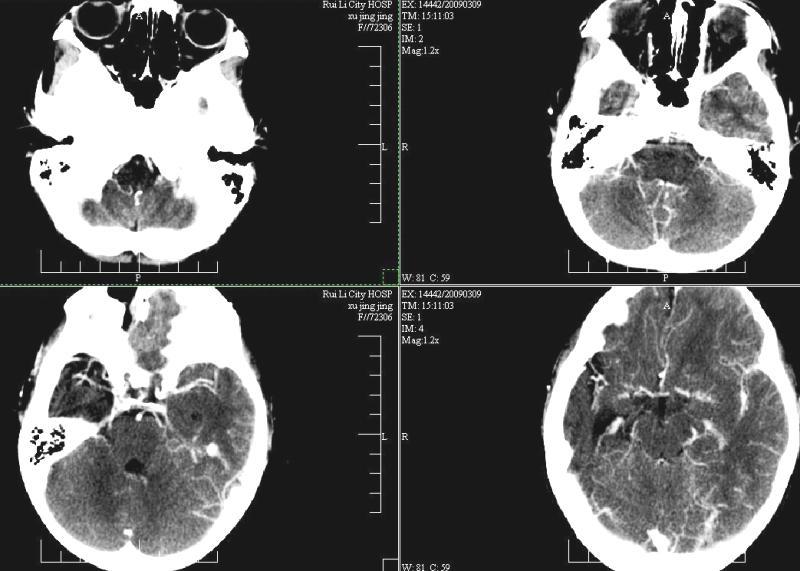

标题: PED1810:F,9岁。头痛,昏倒,一周一次,共半年。 [打印本页]

标题: PED1810:F,9岁。头痛,昏倒,一周一次,共半年。

ct:右顶叶脑软化灶合并右侧大脑半球发育不良可能。

右侧大脑半球脑萎缩。

中线平移,象发育不良

支持楼主!右侧强化明显较左侧低.可能血管引起的吧.

支持楼主!右侧强化明显较左侧低.可能由血管发育不良引起的吧.

支持大脑发育不全----右侧大脑中动脉较对侧细小。建议cta 或mra 检查